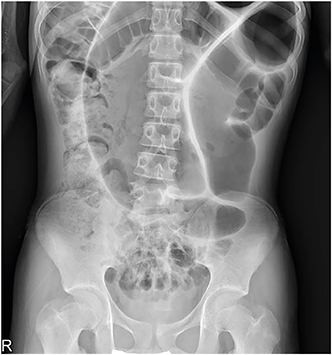

A previously healthy 16-year-old boy with stable vital signs presented with vomiting, diarrhea, distension, and abdominal pain for 4 days. On physical examination, he had abdominal distension with mild abdominal tenderness but without rebound tenderness, and a subtle metallic bowel sound. Laboratory test results were normal. An abdominal radiography revealed a dilated sigmoid colon on the left quadrant (Fig. 1). An abdominal computed tomography (CT) revealed a marked distension of the gas-filled sigmoid colon with twisting of the mesenteric vessels, confirming SV (Fig. 2). A rectal tube was inserted to decompress the volvulus (Fig. 3). He remained asymptomatic thereafter, and discharge was requested. At 2 and 7 months after his initial attack, he was readmitted to the emergency department with the same complaints. Subsequent examinations confirmed the recurrence of SV. The SV was successfully decompressed by means of a rectal tube. His parents again refused surgical treatment; however, 9 months after the first attack, he underwent laparoscopic-assisted sigmoid colectomy. We use a 12 mm port above the umbilicus, a 5 mm right upper quadrant port, a 5 mm left sided port, and a 12 mm right lower quadrant port & left lower quadrant, typically placed 2 fingerbreadths medial and 2 fingerbreadths cephalad to the anterior superior iliac spine. After mobilization of the sigmoid colon, the colon was transected at the rectosigmoid junction with an endolinear stapler (SigniaTM Stapling System; Medtronic, Minneapolis, MN, USA). The umbilical incision was extended. The divided sigmoid colon was exteriorized, and the redundant part was resected. A sigmoid colon section of 34 cm was resected; end-to-end colorectal anastomosis was performed intracorporeally using a circular stapler (ECHELON CIRCULARTM 25 mm Powered Stapler; Ethicon, Bridgewater, NJ, USA). A seromuscular biopsy specimen from the distal colon submitted for histopathologic examination showed normal ganglion cells. On postoperative day 3, he was started on water intake; subsequently, eating progressed successfully. He was discharged without complications on postoperative day 10.

Fig. 2

Coronal abdominal computed tomography showing a dilated sigmoid colon with whirl pattern (arrow) of the mesentery.